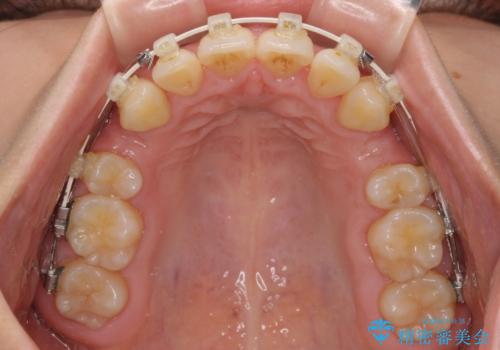

全顎的なデコボコと口元の突出感 ワイヤー装置での抜歯矯正で整った口元に

- 奥歯も含めて全体的なデコボコと前歯の突出感を気にして来院された患者様です。

上下左右第一小臼歯4本を抜歯し、ワイヤー装置にて矯正治療を行うこととしました。

想像以上に咬合力が強く、抜歯したスペースを閉じきるまでに長期間を要することとなりました。

前歯の突出感がなくなり、仕上がりには大変満足していただけました。